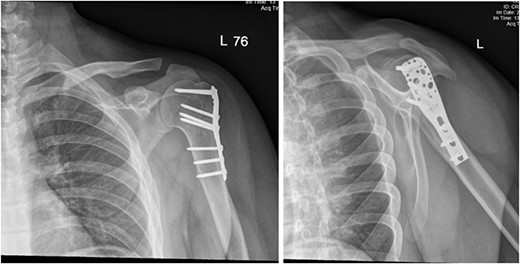

(A) Late follow-up anteroposterior (AP) view of the left shoulder after ORIF. (B) Late follow-up lateral scapula (Y- view) view of the left shoulder after ORIF.